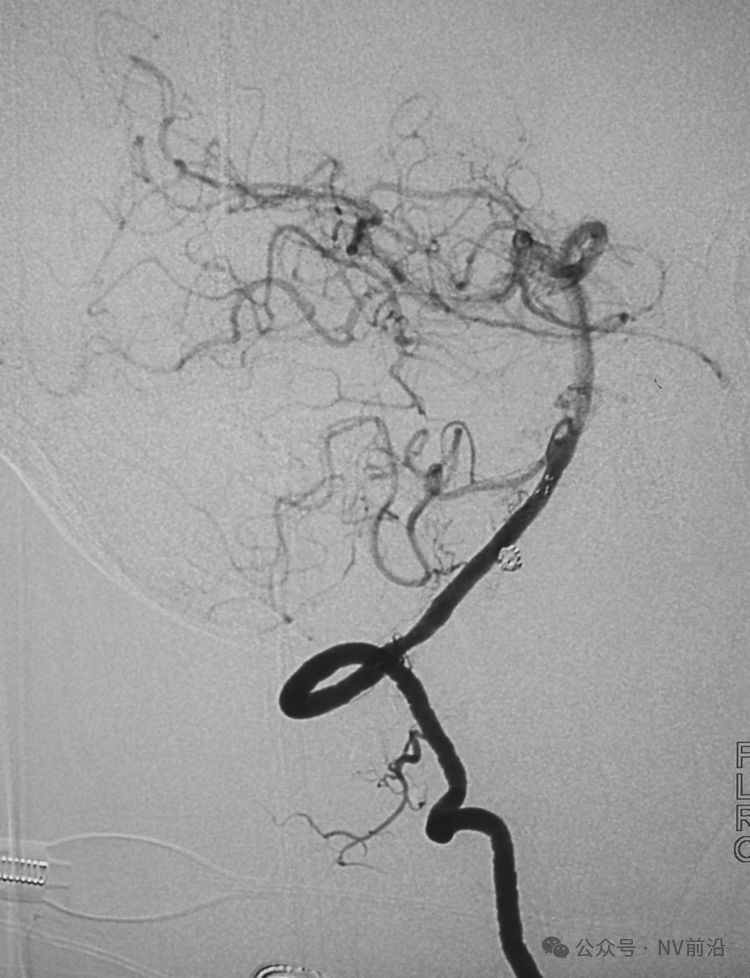

病例二,右侧椎动脉V4段夹层动脉瘤,以头痛入院,21个月前有SAH史。

右椎动脉造影三维重建

Echelon 10微导管头无论塑成C形还是S形,均无法稳定于动脉瘤腔内,遂使用回马枪技术,使微导管成襻通过,管头折返入瘤腔。

跨瘤颈释放Solitaire 4×20支架(蓝线),压住微导管(红线),在支架保护下经返折的微导管送入弹簧圈填塞瘤腔。